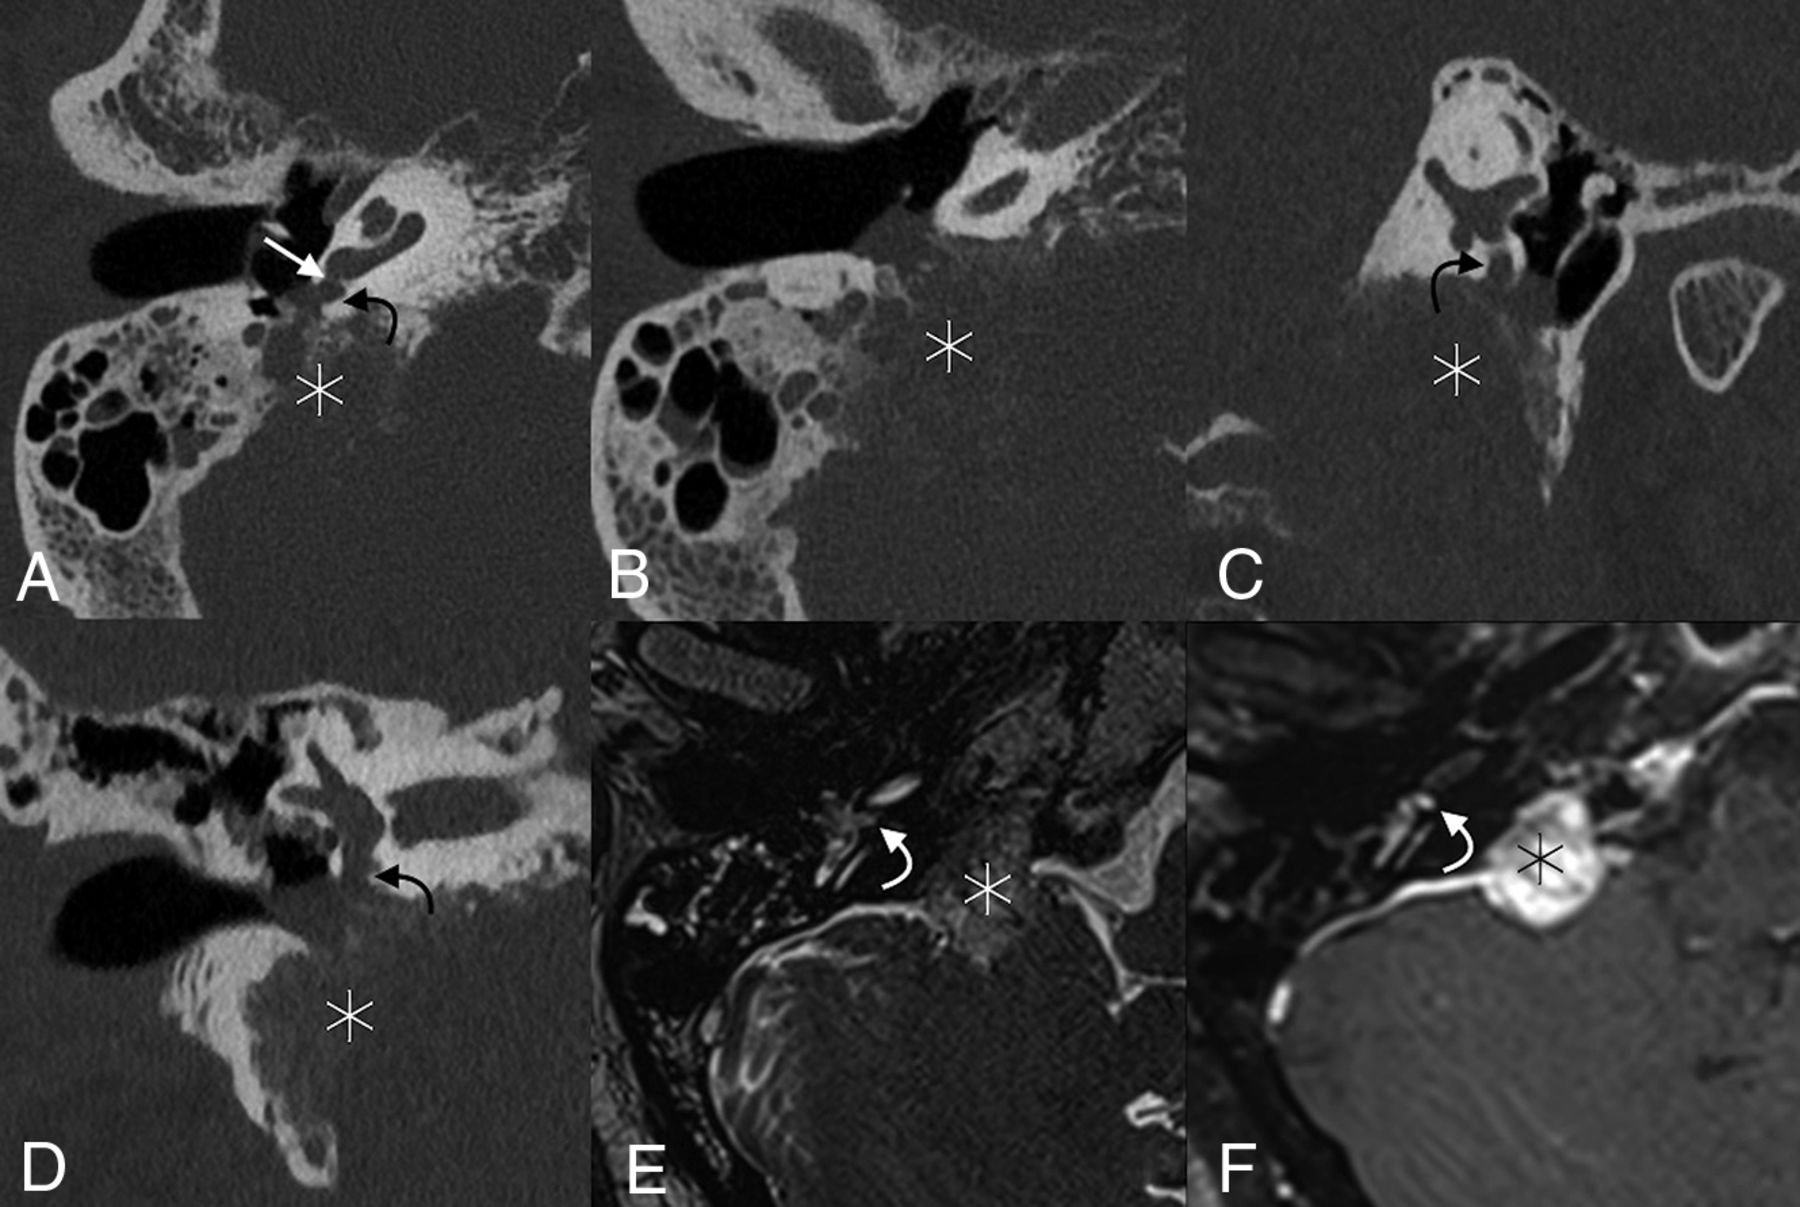

The round window is located along the posterior aspect of the cochlear promontory and measures 1.5–2.1 mm horizontally, 1.9 mm vertically, and 0.65 mm in thickness (Fig 1).1,5 The round window membrane is thicker along its edges and thinner in the middle and is made up of 3 layers: 2 epithelial layers facing the inner and middle ear, respectively, and connective tissue in the core.6 Contrary to its name, the shape of the round window is typically skewed, ovoid, and nonplanar according to a recent study.7 The round window niche is primarily defined by the relatively thin overhanging bone that naturally extends from the promontory. This overhanging bone may obscure complete direct visualization of the round window membrane during routine middle ear surgery and cochlear implantation (Fig 2).8 In addition, most ears have a thin layer of mucosa covering the round window membrane, often called a “pseudomembrane,” that blocks direct visualization of the window if not removed.

Normal round window anatomy. Axial (A), coronal (B), Stenvers (C), and Pöschl (D) images centered on the round window membrane (straight white arrows), situated between the basal turn of the cochlea (black arrows) and the round window niche of the middle ear (curved white arrows). The oval window is closely adjacent (dashed arrow).

Surface-rendered image of a microCT (GE Healthcare, Milwaukee, Wisconsin) of the temporal bone shows the relationship of the round window niche (curved arrow) to the adjacent anatomic structures. Also seen are the lateral semicircular canal (long straight arrow), facial nerve canal (dashed arrow), stapes and oval window (short arrow), and cochlear promontory (asterisk). A indicates anterior; P, posterior.